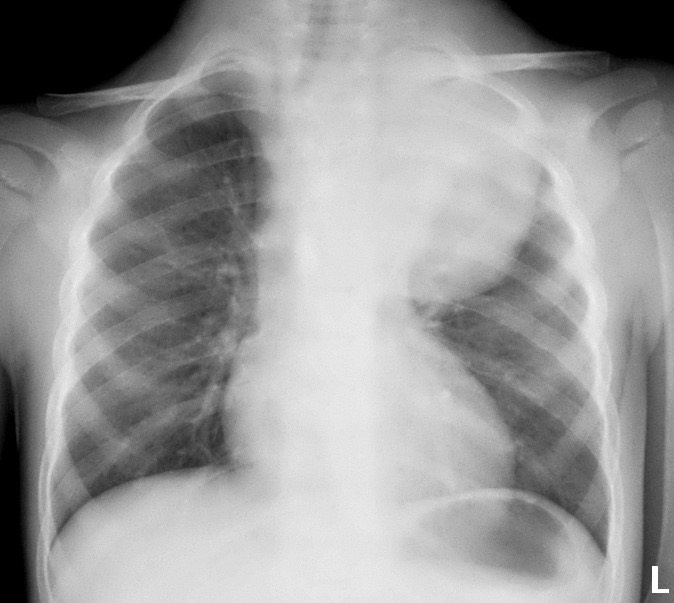

2959. Пациенту 3 лет выполнена рентгенография грудной клетки в прямой проекции, рентгенологическая картина соответствует